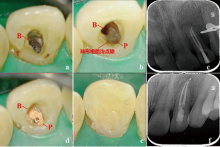

显微根管治疗结合意向性牙再植术治疗双根管上颌侧切牙畸形根面沟1例

Microscopic root canal therapy combined with intentional replantation for the treatment of palatogingival groove in the maxillary lateral incisor with two root canals: A case report

畸形根面沟(palatogingival groove,PGG)是一种位于根面的发育性解剖异常,多见于上颌侧切牙。PGG处牙周组织附着薄弱,易滞留菌斑,引起局部牙周炎症,感染可通过根面沟扩散至牙髓组织,最终导致牙周牙髓联合病变。本文报道了1例因畸形根面沟引起的左上颌侧切牙牙周牙髓联合病变,经显微根管治疗联合意向性牙再植术成功保留患牙,并进行文献回顾,探讨了PGG的诊断要点及治疗方案。

Palatogingival groove (PGG) is a developmental anatomical defect located on the lingual root surface, frequently observed in maxillary lateral incisors. The periodontal attachment in this region is delicate, which makes it vulnerable to plaque accumulation and increases the risk of periodontal inflammation, leading to combined periodontal-endodontic lesions. This article reports a case of a combined periodontal-endodontic lesion in a left maxillary lateral incisor caused by PGG. The tooth was successfully preserved through microscopic root canal therapy combined with intentional replantation. Additionally, a literature review was performed to highlight the key diagnostic features and treatment strategies for PGG.